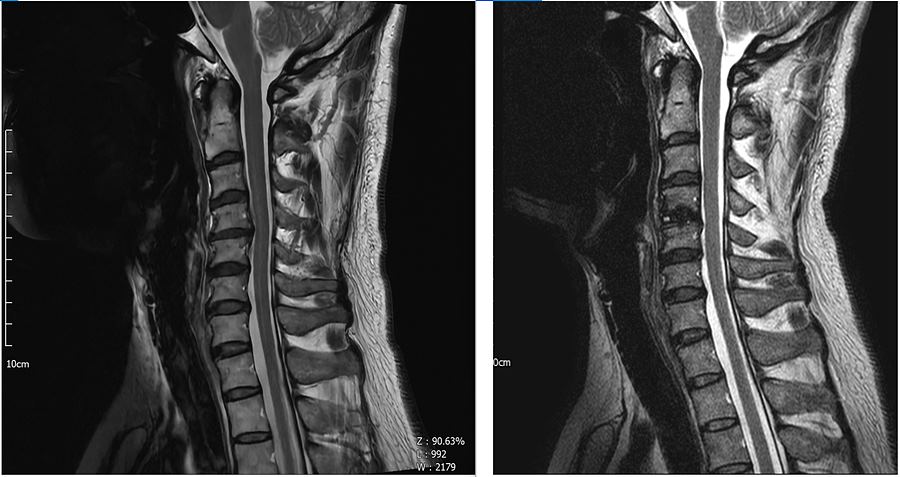

1. MRI 세로 사진 : 오른쪽이 수술후

. C4-C5부분이 약간의 역C자 였던 것도 정상 곡만?처럼 변경이 되었다.

. 교수님께서 앞에도 깍아냈다고 하심.

. 한순간에 이렇게 바뀌었는데 수술 후 극심한 통증을 겪는 것은 당연했다고 생각한다. 수술 후 공황장애같은 것도 겪고 극심한 통증도 겪었던 것들이 신경이 다시 셋업되는 과정이었다고 생각한다.

. 한마디 유합술이기 때문에 앞에 판을 대고 나사 박는게 없다. 교수님께서 이부분 설명해주셨는데 심평원에서 급여 처리 기준이 한마디 유합술은 앞에 판을 대지 않는 것(판을 대는건 두마디부터)이라고 한다. 오히려 한마디인데 판을 댄다면 비급여로 처리된다고 함. 입원 당시 수술 후 목에 이물감의 느낌과 음식물 넘길때 약간의 어려움이 있을 수 있으며 간혹 목소리가 잘 안나올 수 있다고 했었는데 나는 경추 앞에 나사를 판과 함께 박는 것 때문에 그런줄 알았다. 수술 며칠 만에 목넘김이 좋아졌는데 '난 별 문제 없네'하고 생각했는데 앞에 판이 없었기 때문이었다.